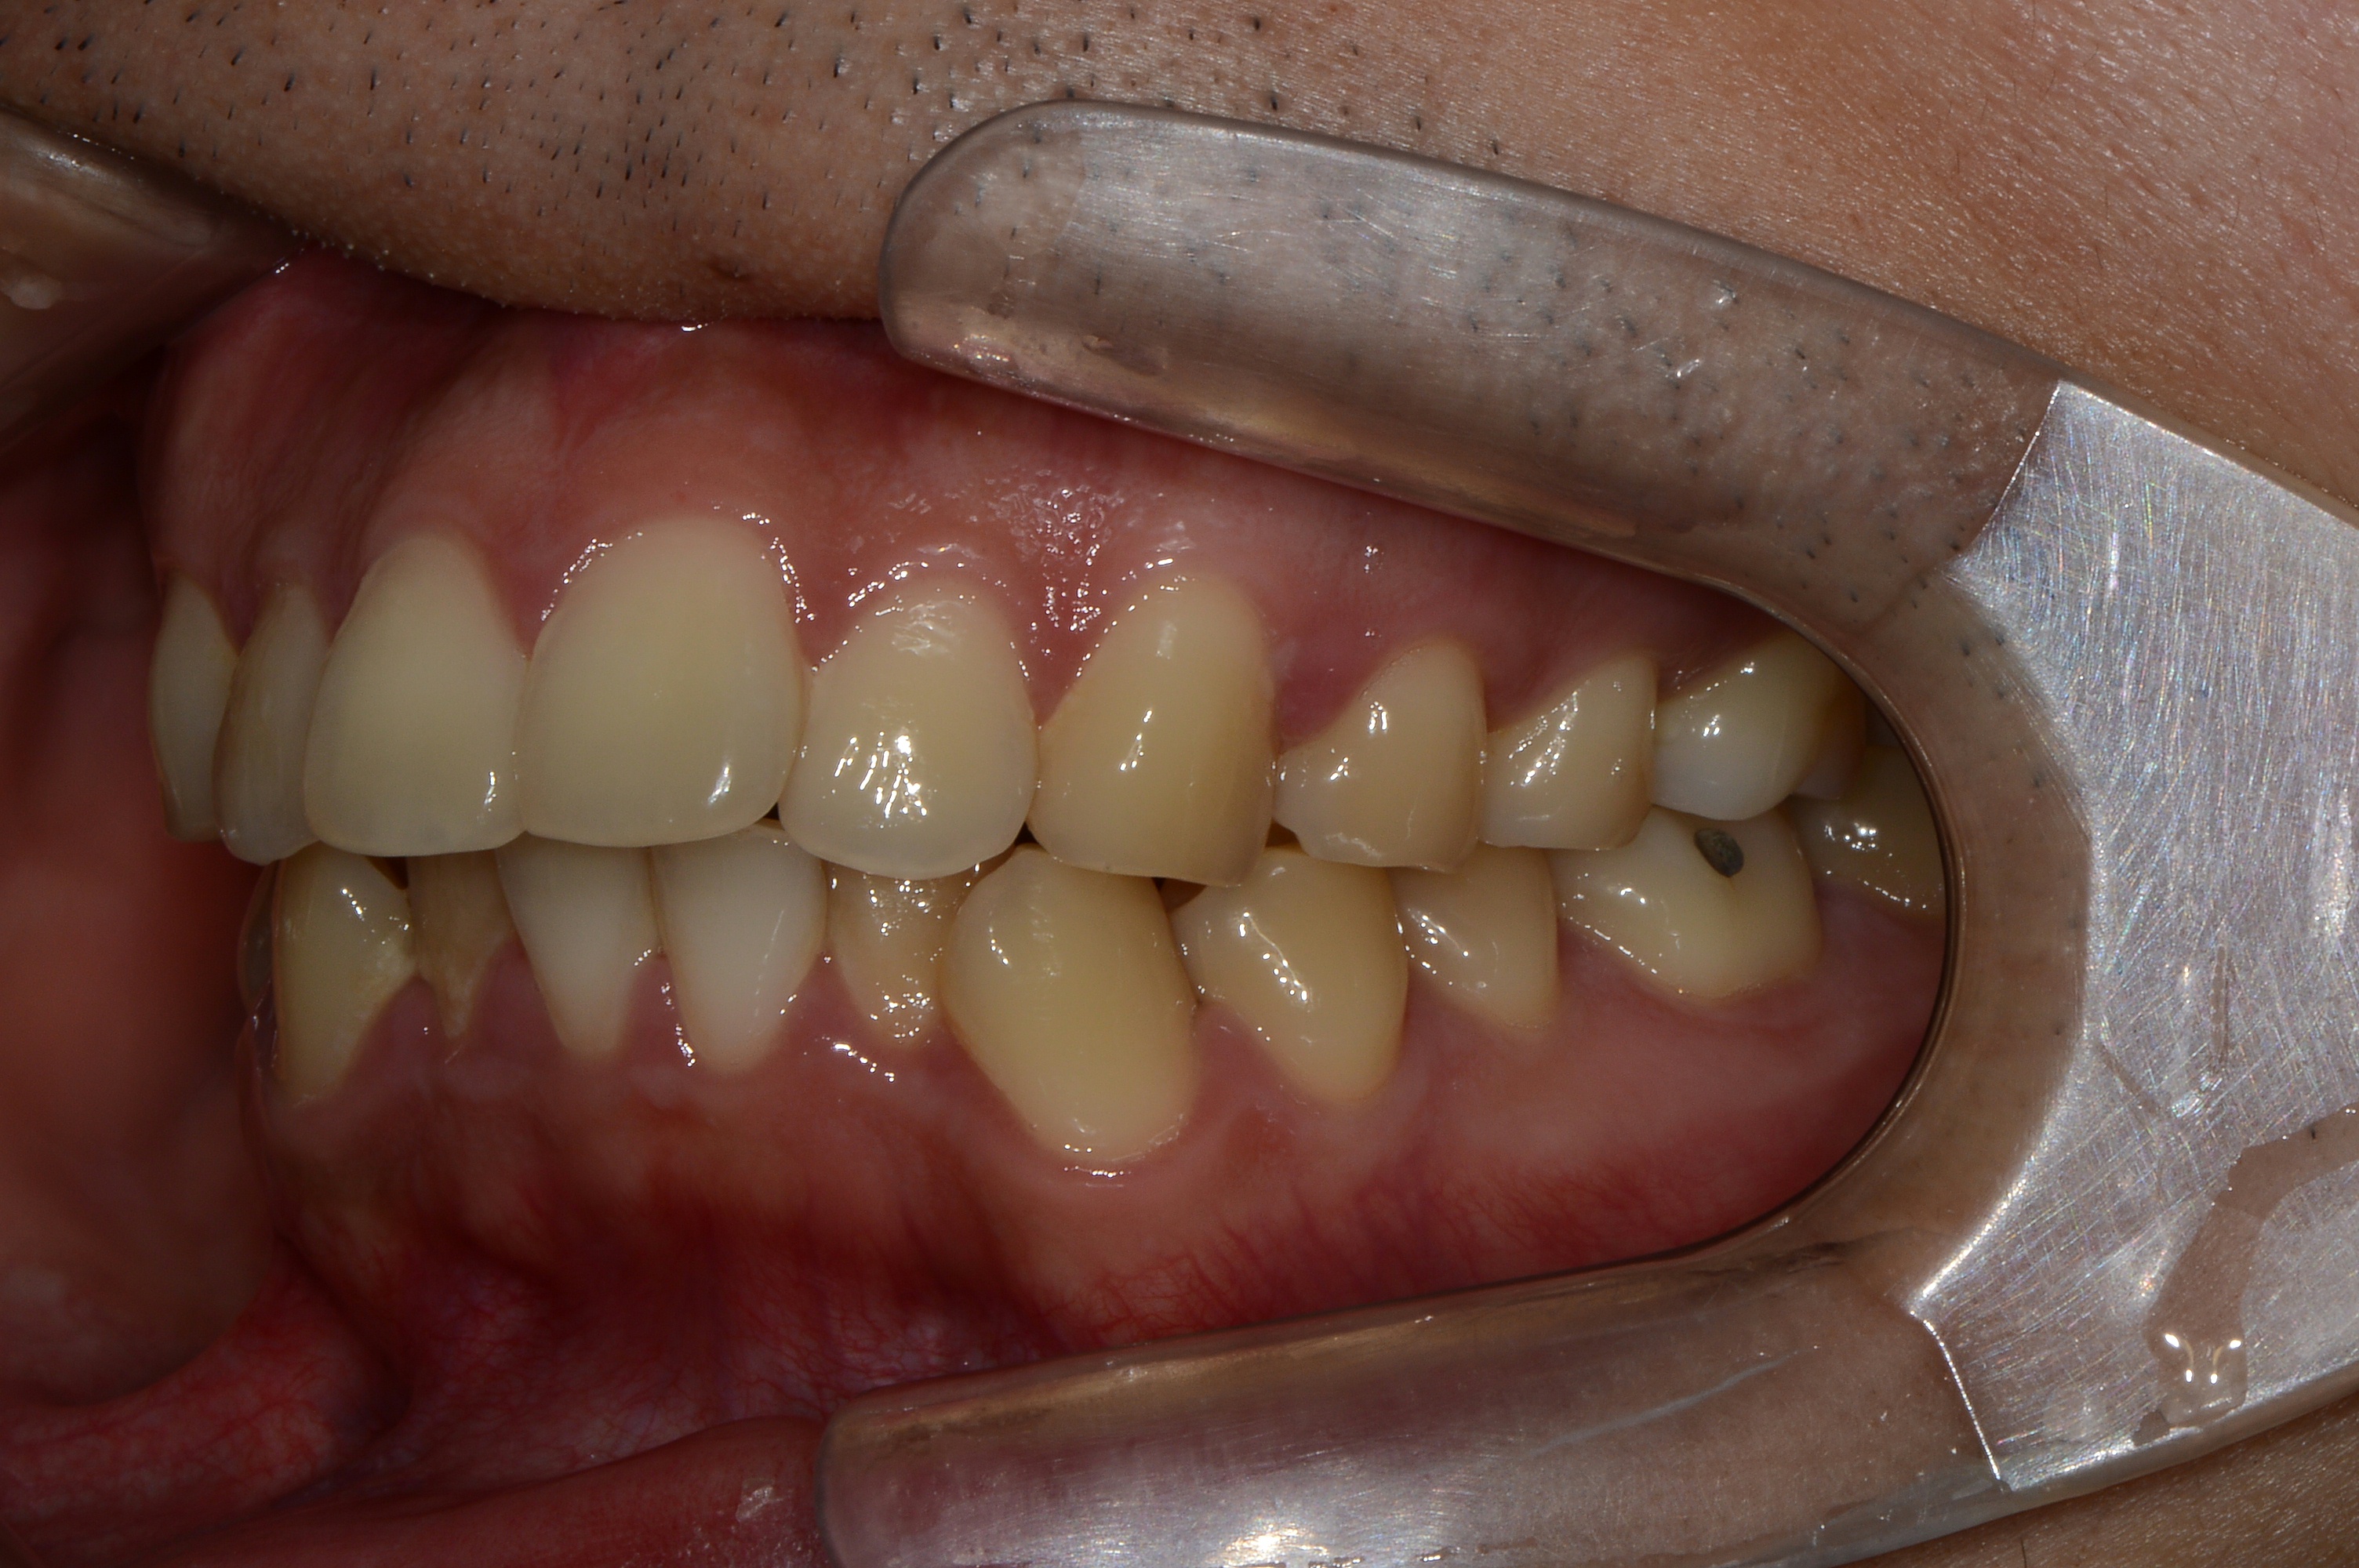

치료 전 사진입니다.